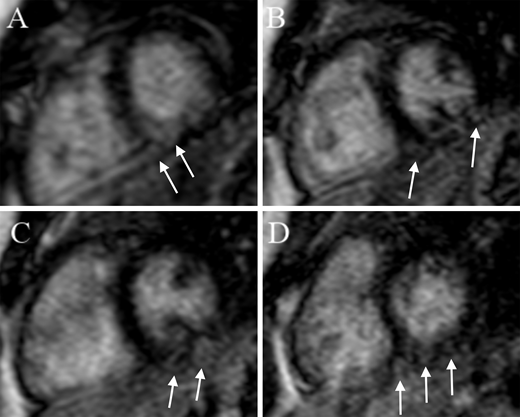

Forty-seven patients (26 with myocardial injury, 21 without) underwent CMR at a mean of 7.2 months after hospitalization. Results are shown in Table 3. Eleven (52%) without myocardial injury and 12 (46%) with myocardial injury had at least 1 abnormality on CMR (odds ratio 0.78 [0.25–2.47], P = .77). One patient, who did not have myocardial injury, had reduced LVEF. Elevated ECV was the most common abnormality (38%), followed by elevated native T1 (19%), and presence of LGE (13%). Only 1 patient had elevated T2. There was not a significant difference between the 2 groups in the prevalence of elevated native T1, elevated T2, elevated ECV, LGE, or CAA. Figure 1 demonstrates representative images of a patient with LGE.

A-D: Short-axis stack demonstrating patchy areas of LGE in the subepicardium and mid myocardium of the LV inferior wall and septum. Arrows indicate areas of LGE.